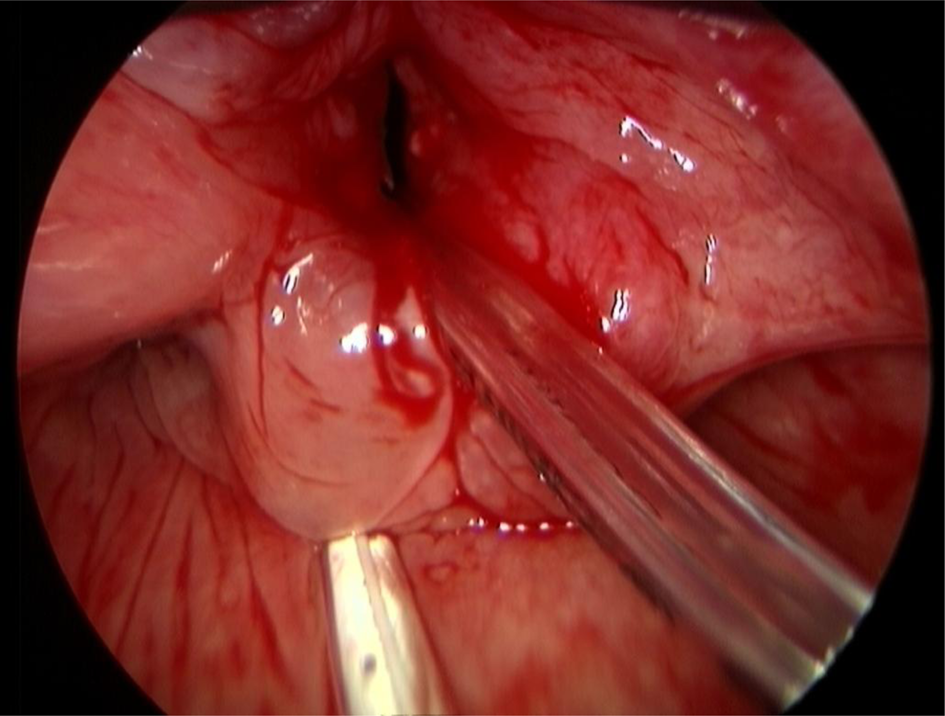

An anterior laryngofissure approach was used to obtain access to the endolarynx and the tumour. A clear view of the submucosal mass and the Tritube in the airway lumen was achieved (Figure 4). The tube did not obstruct the view of, or access to, the tumour. The tumour was resected, including the left arytenoid cartilage. Histology showed a grade I chondrosarcoma.

Fig. 4. Opening of the laryngofissure with inspection of the endolarynx. The Tritube is seen in situ. The tumour is seen on the left side. The left vocal fold was stretched over the tumour and the vestibular folds were pushed up cranially.